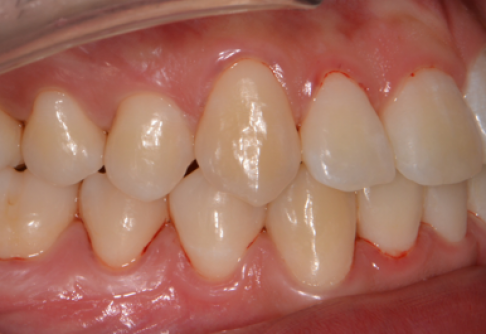

After

위 치료 사례는 굿프렌즈치과에서 직접 치료를 받은 환자 분의 사례로 직접 동의를 얻어 게재되었습니다.

치료사례 더보기 +